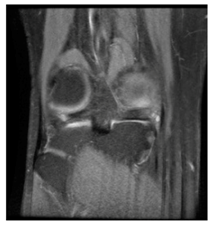

In this section, we present and analyze the results obtained with the proposed method, and compare it to methods proposed in similar works. The proposed watermarking system is implemented using MATLAB and executed on a Windows machine with the following characteristics: Intel R Core i5 processor, 4 GHz, 4 GB RAM, and Microsoft Windows 8 Professional operating system platform. In our experiments, we have used DICOM images of size 512 × 512 pixels as shown in Table 1.

Table 1.

Original images.